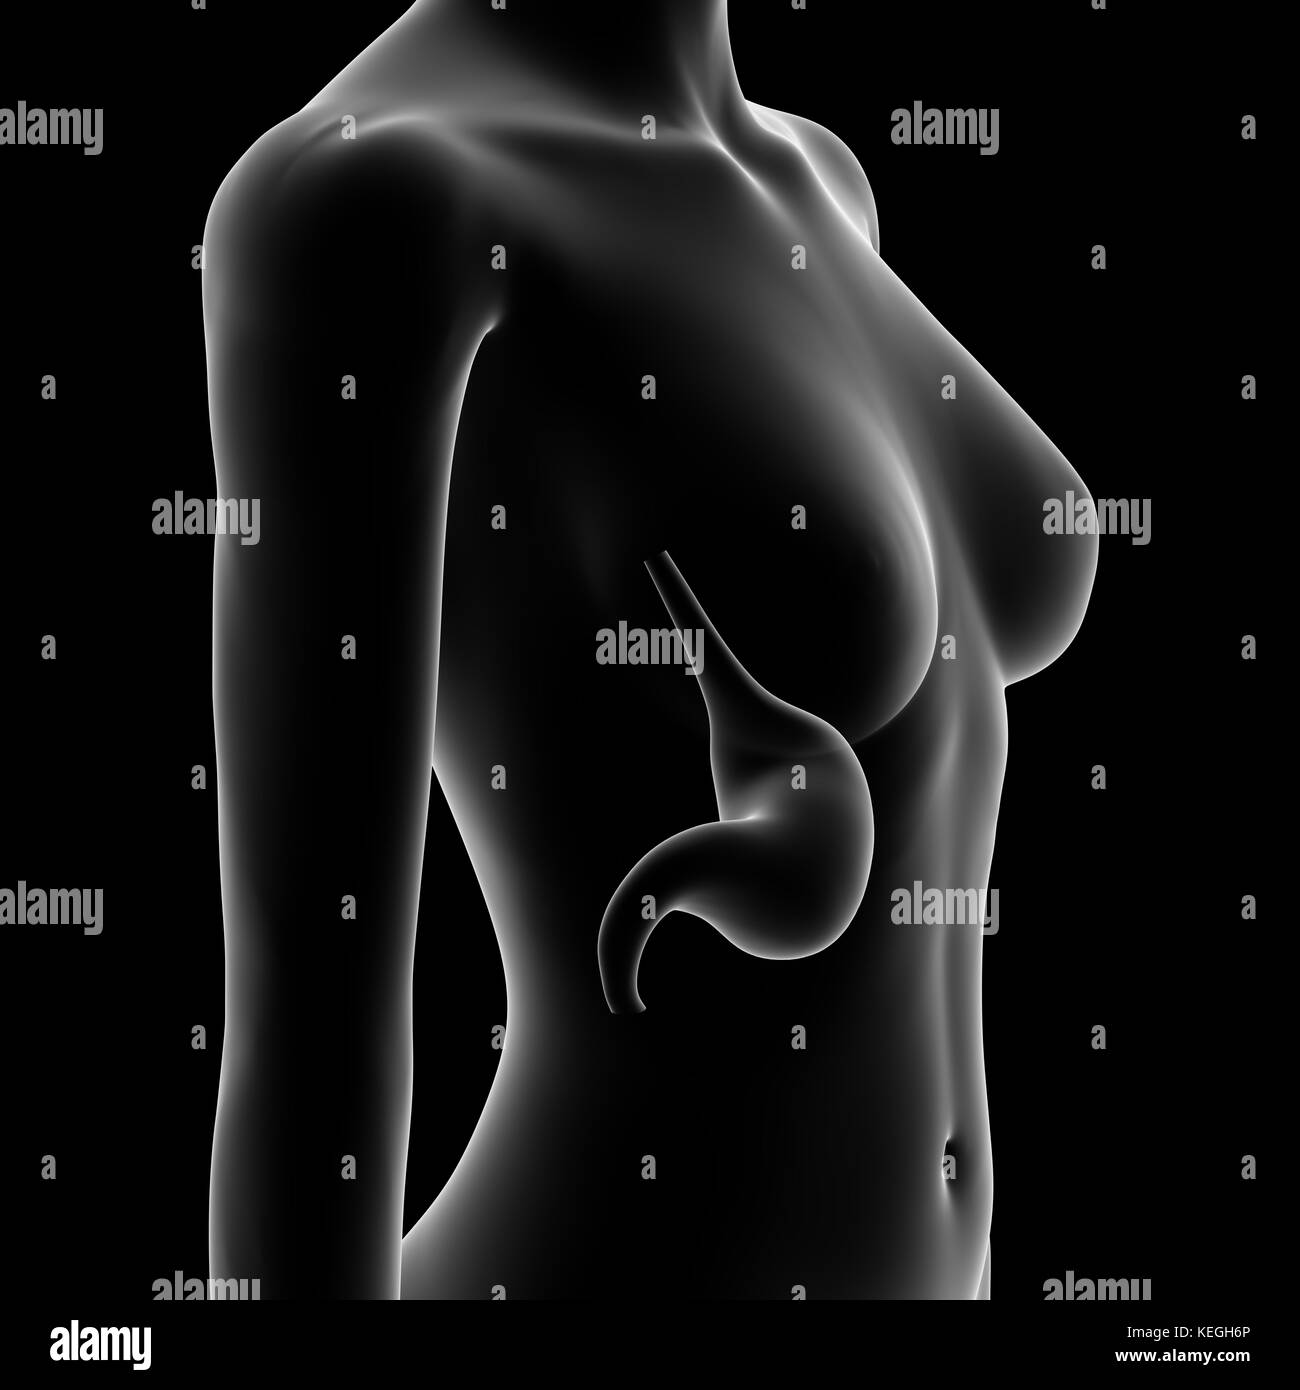

Illustration of Female Internal Organs Stock Photohttps://www.alamy.com/image-license-details/?v=1https://www.alamy.com/stock-photo-illustration-of-female-internal-organs-135006887.html

Illustration of Female Internal Organs Stock Photohttps://www.alamy.com/image-license-details/?v=1https://www.alamy.com/stock-photo-illustration-of-female-internal-organs-135006887.htmlRMHRJ2JF–Illustration of Female Internal Organs

Illustration of Female Internal Organs Stock Photohttps://www.alamy.com/image-license-details/?v=1https://www.alamy.com/stock-photo-illustration-of-female-internal-organs-135006572.html

Illustration of Female Internal Organs Stock Photohttps://www.alamy.com/image-license-details/?v=1https://www.alamy.com/stock-photo-illustration-of-female-internal-organs-135006572.htmlRMHRJ278–Illustration of Female Internal Organs

Stomach, Medical Illustration Stock Photohttps://www.alamy.com/image-license-details/?v=1https://www.alamy.com/stock-image-stomach-medical-illustration-163863246.html

Stomach, Medical Illustration Stock Photohttps://www.alamy.com/image-license-details/?v=1https://www.alamy.com/stock-image-stomach-medical-illustration-163863246.htmlRFKEGH6P–Stomach, Medical Illustration